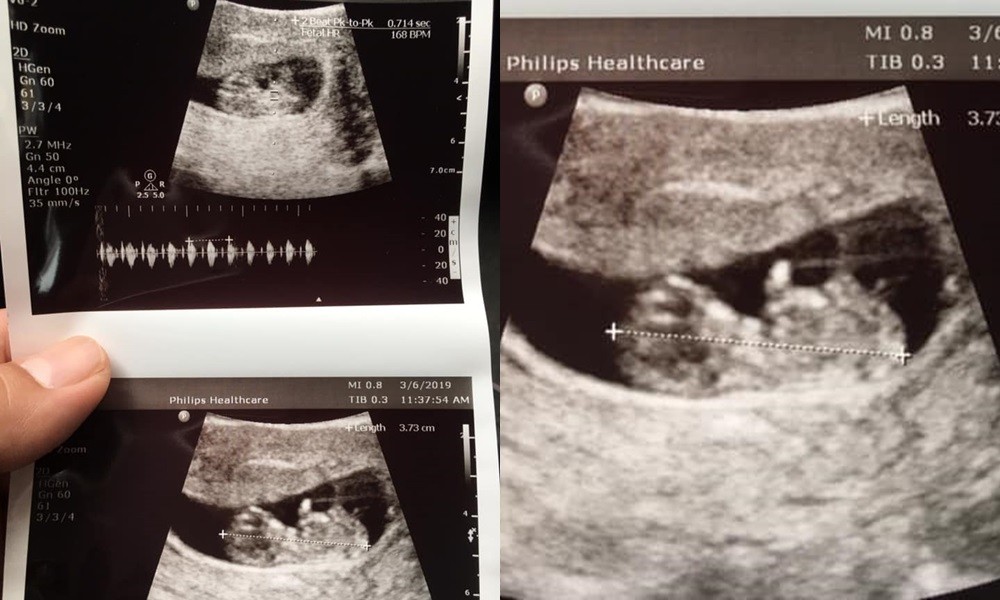

▲原PO拿到老婆給他的超音波照。(圖/翻攝自爆廢公社)

「我老婆早上拿這個給我看,說肚子不舒服」,一名男網友在臉書《爆廢公社》表示,老婆去照腹部超音波,事後拿給他2張黑白照片,讓他忍不住發文問「請問這個是腸胃炎嗎?」看到照片後,其他人紛紛留言笑說「老婆連續10個月肚子都會不舒服」、「很嚴重,這會出人命」、「這個很難醫治~要長期醫療費」。

仔細看看照片,這2張腹部超音波的黑白照片清楚照出原PO老婆「肚子裡有東西」,但那既不是什麼腫瘤、更不是宿便,而是2人愛的結晶「小寶寶的胚胎」。而這位爸爸雖然在《爆廢公社》中求問「這是腸胃炎嗎?」但卻在個人臉書向「未來兒子」喊話「小子安分一點,不要再讓你媽媽不舒服了,不然卸貨先打一頓」,原來根本就是「假求救真炫耀」。

▲原來是「兒子」讓老婆的肚子不舒服啊 XD(圖/爆廢公社)